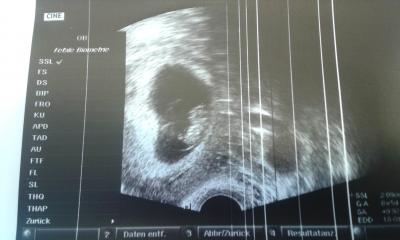

Hatte heute morgen meinen heiß ersehnten Termin. Dem Käfer geht es gut. Ist 2 cm groß und das Herzchen bubberte ordentlich. Und es hat sich sogar schon bewegt. Zu schön anzuschauen. Blutwerte vom letzten Mal waren alle soweit ok. Nur bei Toxoplasmose bin ich ohne immunschutz. Nächster Termin ist dann am 10.7. . Dann bin ich dann bei 12+4.

Das ist auch ein schönes Foto. Freut mich, dass auch bei dir alles gut ist. Wow, du konntest schon Bewegungen sehen? Darf ich mal ganz dumm fragen, was dein Käfer gemacht hat? Ich hab ja nichts sehen können, freu mich schon auf das Screening in 2 Wochen, da haben meine beiden Großen schon eifrig gestrampelt. LG und schön weiter brüten Ach so, am 10.07. habe ich mein Nackenfaltenscreening. :-)

Tolles Foto ! :) Und schoen das alles gut ist